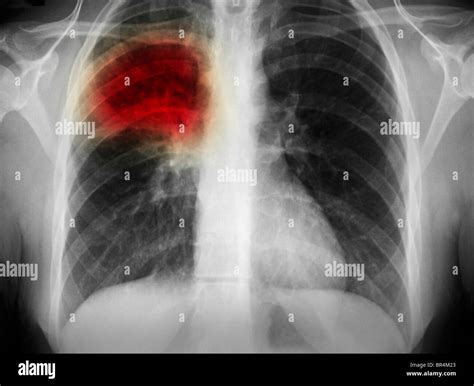

How Pneumonia Appears on an X-ray

Healthy lungs appear mostly black on an X-ray because they are filled with air. When pneumonia is present, the areas of the lung affected by the infection appear as opaque, white, or cloudy patches. This phenomenon is known as consolidation. It occurs because the air in the alveoli has been displaced by fluid, inflammatory cells, or debris, which blocks the passage of X-rays.

• Lobar Pneumonia: This appears as a distinct area of consolidation restricted to one lobe of the lung. It is often associated with bacterial infections.